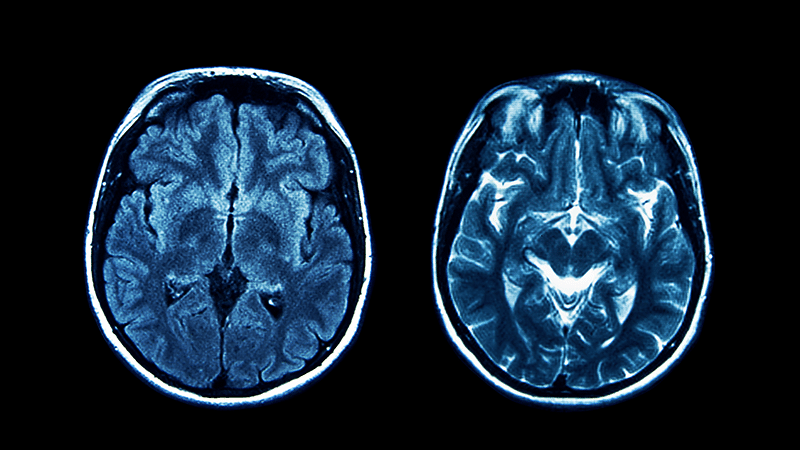

Research using adult stem cells offers hope for treating strokes and vascular dementia, scientists believe.

In a pioneering study at the University of Cambridge, academics created a model of diseased brain blood vessels from patients’ reprogrammed skin cells. They then successfully reversed the damage.

Cerebral small vessel disease (SVD) contributes to almost half of dementia cases worldwide and causes one in five of the most common type of stroke.